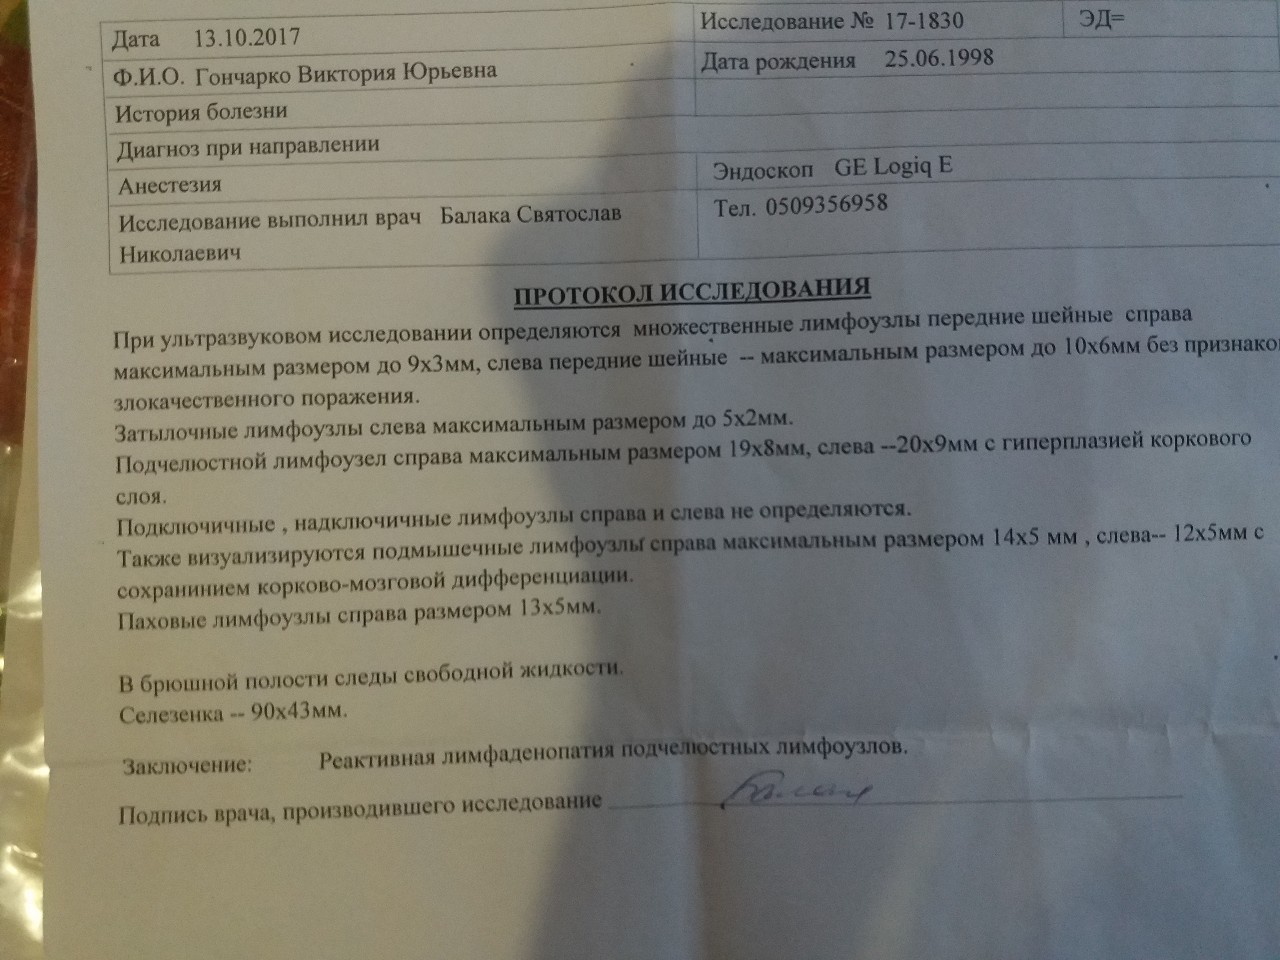

Мезентериальные лимфатические узлы: УЗИ и диагностика

Раздел: Лаборатория идей